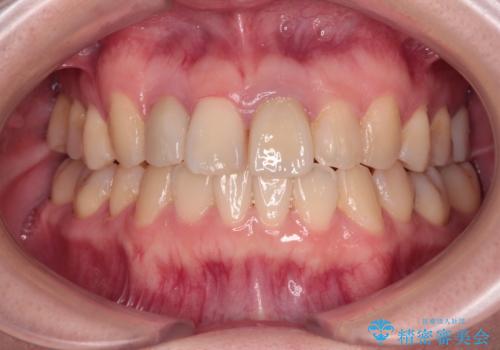

虫歯治療ついでに歯並びの後戻りを改善 インビザラインによる矯正治療

- 奥歯が痛いとのことで来院された患者様です。

上顎親知らず周辺の炎症と、神経組織の失活した歯の炎症による痛みが認められたため、親知らずの抜歯と根管治療を行いました。

根管治療を行った歯はクラウンによる補綴治療が必要となりますが、高校生の頃に行った矯正治療の後戻りも気になるとのことで、補綴治療を行う前に矯正治療を行うこととしました。

後戻りは軽度であり、インビザラインにて歯列を整え、その後にオールセラミッククラウンにて補綴治療を行うこととしました。

ご家庭やお仕事の都合で通院が途絶えた時期があり、治療は長期間となりましたが、無事に終えることができました。